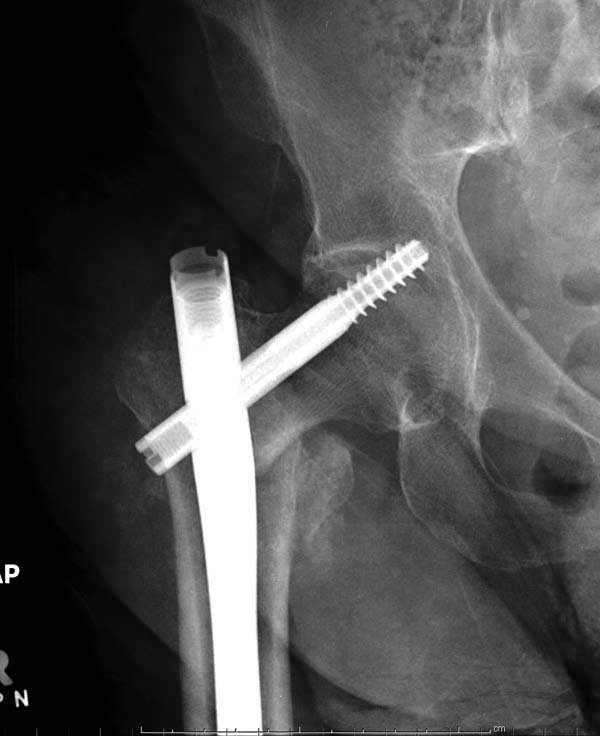

Первые снимки показывают технические погрешности установки DHS. Не была достигнута репозиция, конечность в флексии и шейка в ротации. Сегодня все меньше обращают внимание на параметры для оценки репозиции (S контуры Lowell в обеих проекциях и Garden Alignment Index, в норме 155 и 180 градусов), хотя такие простые тесты помогли бы дорепонировать смещение. Винт находится сзади в головке, что при нагрузке поменяет вектор и вместо компрессии в линии перелома срежет головку-Cut Out!

В зависимости от дистанции линии перелома и латерального кортекса надо использовать разной длины barrel, т.е. конец баррели не должен доходить до пределов перелома. Здесь конец длинного ствола упирается в медиальный фрагмент, что мешает созданию компрессии, а более короткий barrel создал бы запас для компрессии. В боковой пластине вместо 4х можно было ограничится двумя шурупами, потому что головка шурупа в 4.5 мм выдерживает давление до 350 кг.